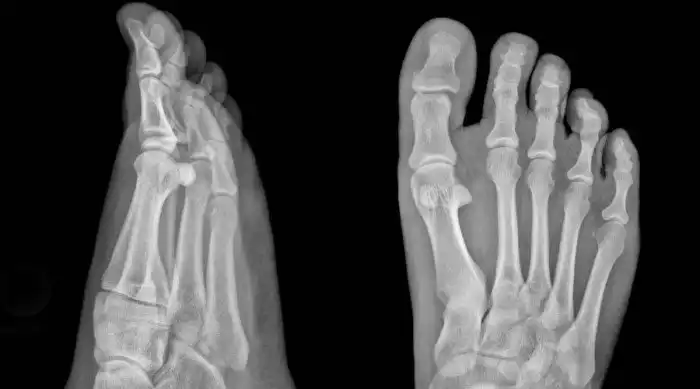

Что это такое

Доведенное до третьей степени плоскостопие приводит к серьезной деформации стопы. Отеки появляются ежедневно, ходить становится трудно даже в пределах комнаты. Теперь без ортопедических ботинок обойтись не получится, иначе будет только хуже.